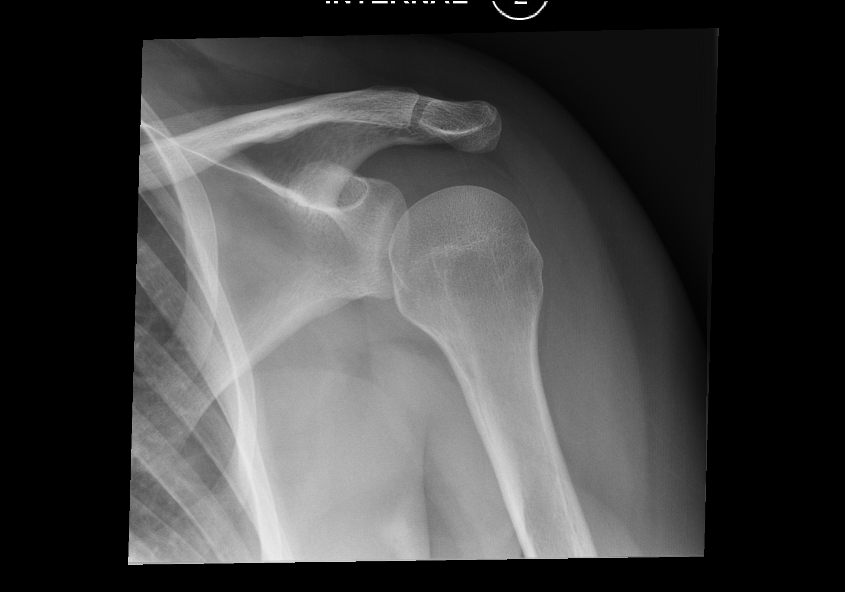

| Anterior (subcoracoid most common) | ~95% | Humeral head medial and inferior to glenoid; loss of normal glenohumeral overlap; head projects below coracoid on AP; Y-view shows head anterior to glenoid center | Hill-Sachs defect (posterolateral head impaction, |

| Hill-Sachs | Anterior | Posterolateral humeral head impaction against the anteroinferior glenoid rim; cortical depression | XR: AP with internal rotation; CT or MRI; assess "on-track" vs "off-track" to determine instability risk |

- Hill-Sachs defect — location and size; is it "on-track" or "off-track"?

- Bankart fracture — osseous fragment size as percentage of glenoid width

- Greater tuberosity fracture: present / displaced (>5 mm in general; >3 mm in young athletes)